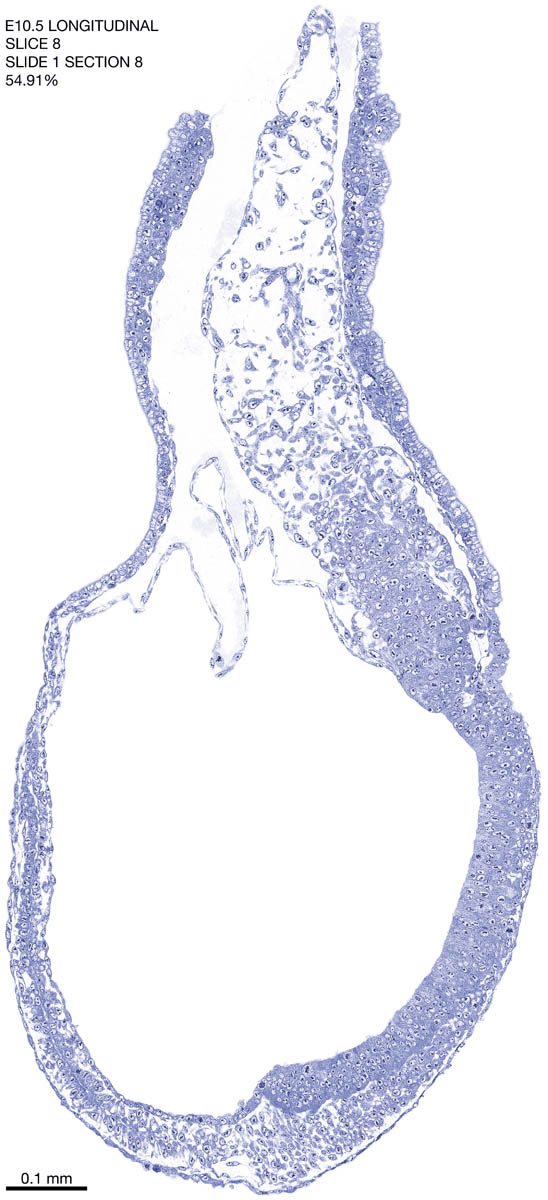

E10.5 Longitudianal Archive This page contains jpg files of ALL SLICES (each 3µm thick) that were scanned of the E10.5 longitudinally cut specimen. Download: Large | High Res Download: Large | High Res Download: Large | High Res Download: Large | High Res Download: Large | High Res Download: Large | High Res Download: Large | High Res Download: Large | High Res Download: Large | High Res Download: Large | High Res Download: Large | High Res Download: Large | High Res Download: Large | High Res Download: Large | High Res Download: Large | High Res Download: Large | High Res Download: Large | High Res Download: Large | High Res Download: Large | High Res Download: Large | High Res Download: Large | High Res Download: Large | High Res Download: Large | High Res Download: Large | High Res Download: Large | High Res Download: Large | High Res Download: Large | High Res Download: Large | High Res Download: Large | High Res Download: Large | High Res Download: Large | High Res Download: Large | High Res Download: Large | High Res Download: Large | High Res Download: Large | High Res Download: Large | High Res Download: Large | High Res Download: Large | High Res Download: Large | High Res Download: Large | High Res Download: Large | High Res Download: Large | High Res Download: Large | High Res Download: Large | High Res Download: Large | High Res Download: Large | High Res Download: Large | High Res Download: Large | High Res Download: Large | High Res Download: Large | High Res Download: Large | High Res Download: Large | High Res Download: Large | High Res Download: Large | High Res Download: Large | High Res Download: Large | High Res Download: Large | High Res Download: Large | High Res